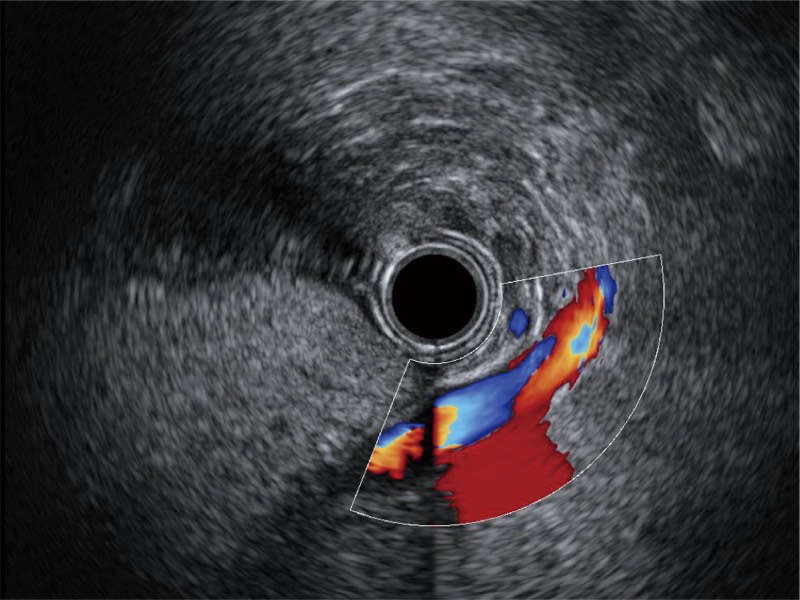

可人为将灰阶图像转变成彩色的显示方式,增强人眼对于不同回声强度的敏感度,主观上增加了图像分辨率

食管内间质瘤清晰显像

清晰显示胆总管及周围血管分布

肝左叶和肝静脉的横截面